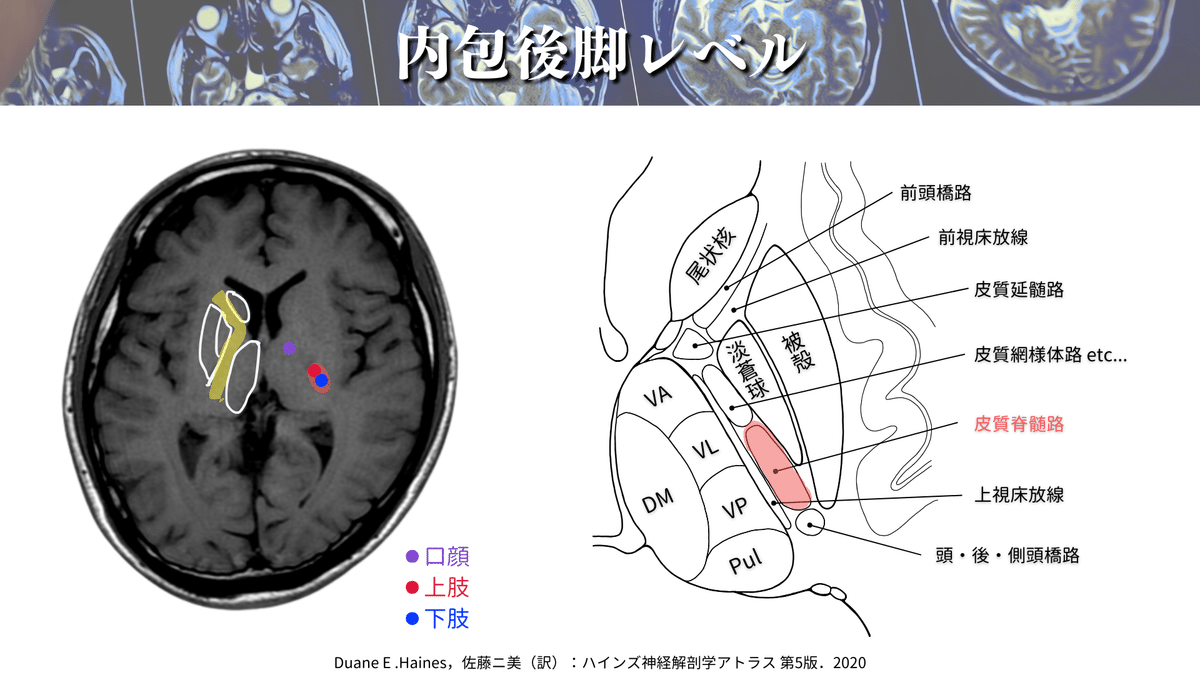

内包後脚レベル

このレベルもよく養成校の授業や参考書で解説される部分ではないでしょうか🤔?

まずは大まかなCSTの走行を見ていきましょう👀

黄色の部分が内包でして、内包が折り曲がるところが内包膝と言いますよね🦵

内包膝の前方を内包前脚、後方を内包後脚と言いまして、この内包後脚の部分のさらに後半分あたりをCSTが走行していきます🏃♀️

解像度を上げて見てみると、、、🔍

口顔の部分の運動線維の皮質延髄路は、内包膝を通って下降していきます👄

つまり、内包後脚部分を通るのは上下肢・体幹のCSTになるということですね✋🦶

もっとわかりやすく見てみると〜👁️✨

こんな風になります😆

赤く染めた部分がCST(上下肢・体幹)の通過位置になります👍